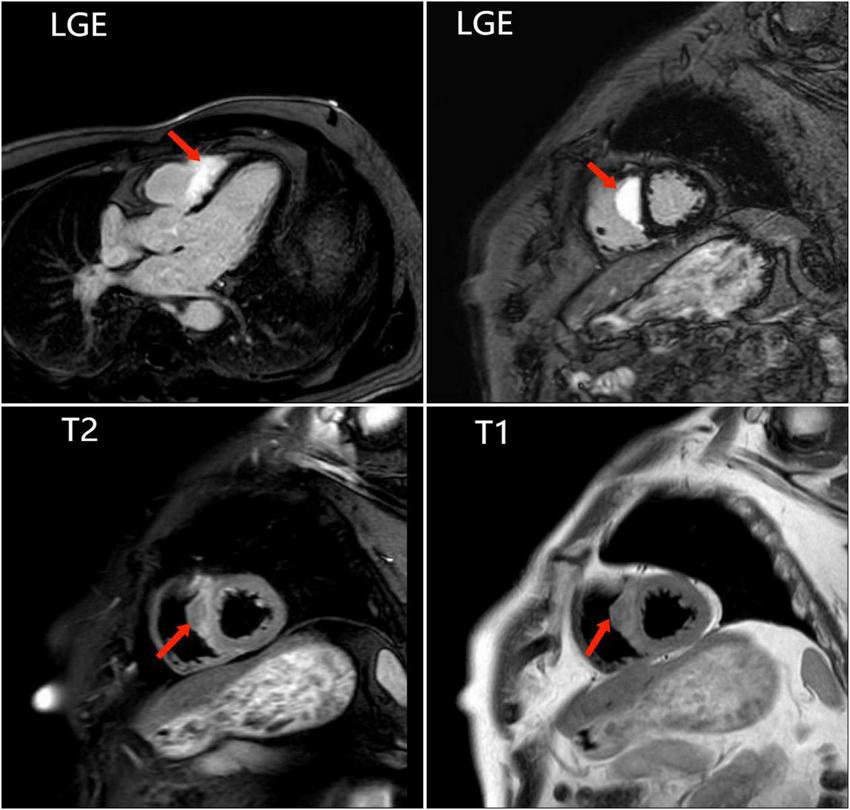

FIGURE 3

The last cardiac magnetic resonance is used for accurately locating the lesion and improving the success rate of the endomyocardial biopsy. Images show abnormal signals in the right ventricular surface of the ventricular septum, and significant LGE.

To further clarify the cause of arrhythmia, we performed an EMB. To accurately locate the lesion and improve the success rate of the EMB, the patient underwent the last CMR (Figure 3). Using CMR imaging guidance, EMB was taken from interventricular septum tissue of the right ventricle. EMB revealed a large number of epithelioid nodules composed of epithelioid cells, multinucleated giant cells, and lymphocytes in the myocardium and endocardium. However, no necrotic tissue was found on acid-fast staining (–) (Figure 4). Based on the clinical manifestations, imaging data, and pathological features, we diagnosed the patient with ICS. Thereafter, the patient received dual-chamber implantable cardioverter defibrillator to prevent sudden death, while prednisone (35 mg/d) was administered to treat sarcoidosis. Additionally, spironolactone (20 mg/d) and daglitazine (10 mg/d) were administered to delay ventricular remodeling.